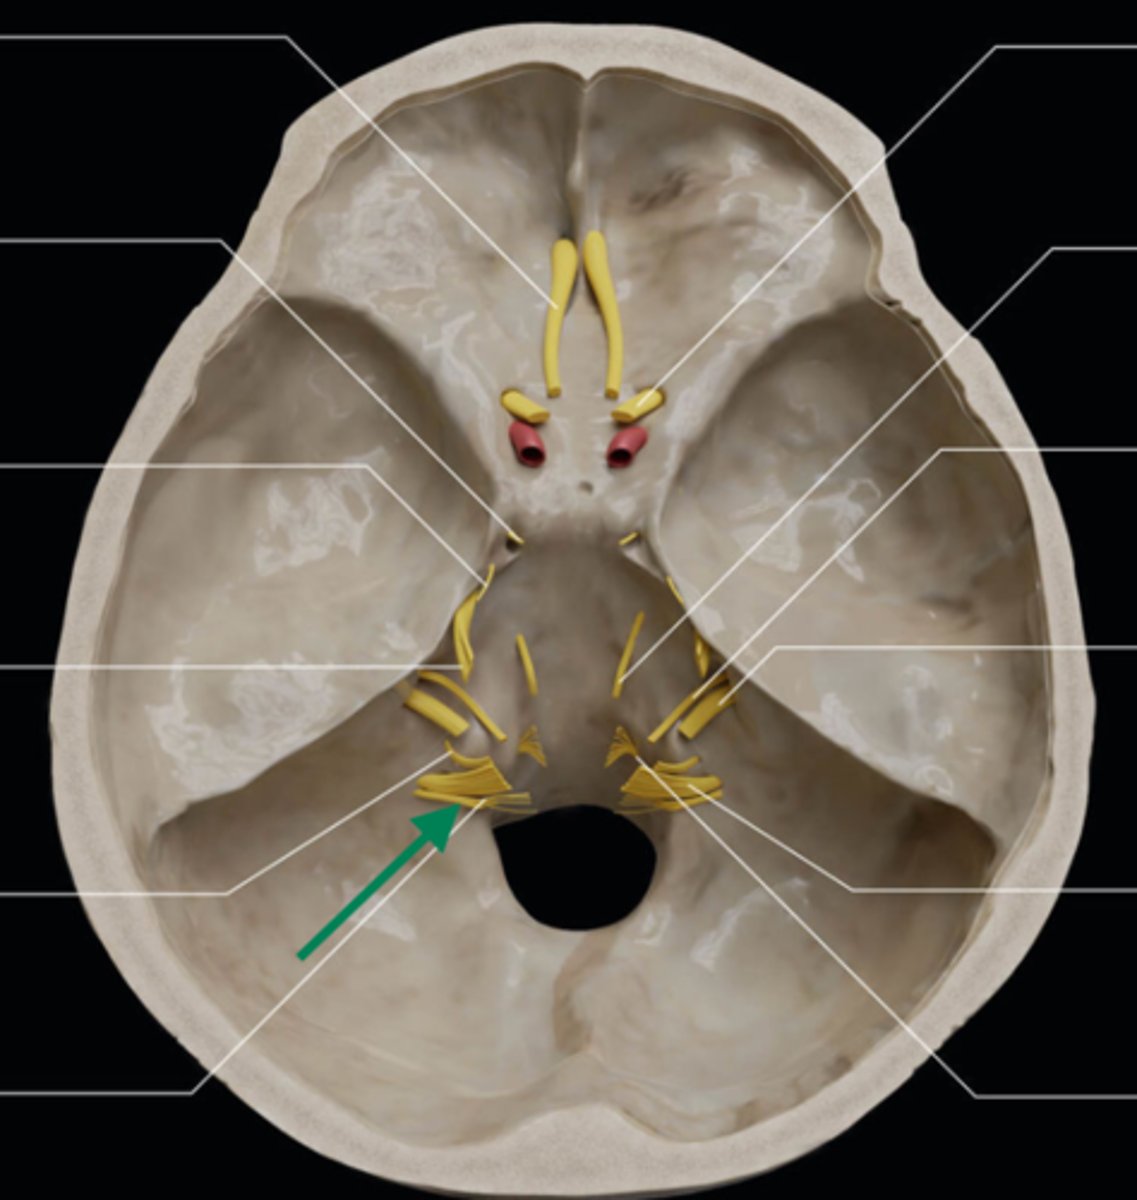

olfactory bulb

olfactory tract

optic nerve (CN II)

internal carotid artery

oculomotor nerve (CN III)

trochlear nerve (CN IV)

abducent nerve (CN VI)

trigeminal nerve (CN V)

facial nerve (CN VII)

vestibulocochlear nerve (CN VIII)

glossopharyngeal nerve (CN IX)

vagus nerve (CN X)

accessory nerve (CN XI)

hypoglossal nerve (CN XII)

optic chiasm

trigeminal ganglion

anterior cranial fossa